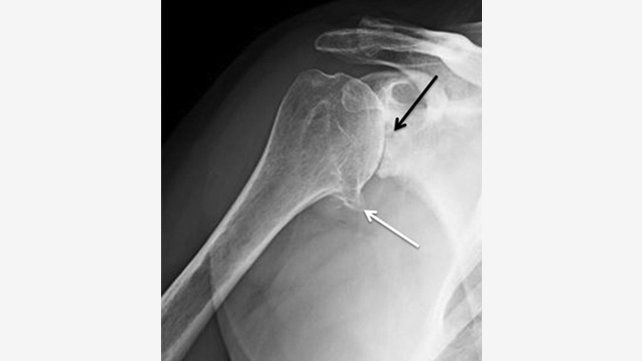

X-rays are necessary for diagnostic purposes and surgical planning.

Shoulder x-ray showing loss of joint space (black arrow) and arthritic spurring (white arrow).

During the examination of your shoulder, your physician will assess shoulder joint stability, limitation of motion, and shoulder strength, including rotator cuff strength. X-rays are necessary for diagnostic purposes and surgical planning and CT imaging is used to further define bony and soft tissue anatomy.